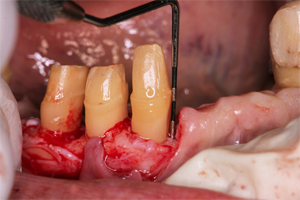

抜歯と再生療法:下顎前歯部、左側臼歯部

歯根の先まで骨の吸収がみられた下顎左側臼歯部は、やむを得ず抜歯を診断しました。

抜歯前

下顎前歯部も同様に抜歯を診断、抜歯後再生療法を実施しました。

骨の吸収が著しい下顎前歯部の3本

残存した歯を利用して可能な限り固定式のブリッジで対応できるよう歯周組織の再生を図りました。(再生療法)

抜歯した部位に

再生療法を実施

縫合